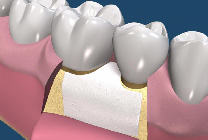

牙周再生手術是一種要求較高的牙周手術,其成功取決於多種條件的滿足,這些條件是:嚴格的適應證選擇;牙齦的炎症被有效控制;骨內袋中的肉芽組織應當儘可能被清除;生物膜在齦溝“領口”處應與牙根面盡量密合,以保證無齦上皮長入;生物膜與牙根之間應保持充分的空間,即足夠的膜根間隙;齦瓣應將生物膜完全覆蓋;術前術後有效的菌斑控制。(圖07-11)

圖7